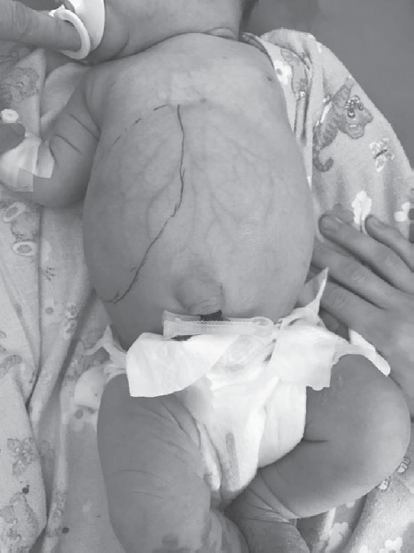

Случай 1. Девочка Е., новорожденная. Антенатально патологии не выявлено. После рождения при осмотре отмечалось увеличение окружности живота, подчеркнутость венозной сети на передней грудной и брюшной стенке, пальпаторное увеличение печени и селезенки, множественные гемангиомы кожи туловища, головы и конечностей. В клиническом анализе крови выявлена тромбоцитопения. Для дообследования и лечения ребенок переведен в отделение патологии новорожденных Перинатального центра СПбГПМУ. При поступлении состояние пациента стабильное, был проведен мониторинг: витальные функции — без особенностей. При осмотре на коже передней грудной и брюшной стенки отмечалась выраженная подчеркнутость поверхностных венозных сосудов. Живот мягкий, симметричный, не вздут, но увеличен в объеме, при пальпации безболезненный, пальпируется увеличенная печень, выступающая до 6 см из-под края реберной дуги (рис. 2, 3), край печени плотный, закруглен, селезенка не пальпируется.

Рис. 2. Внешний вид пациентки Е. при поступлении. Линией обозначены пальпаторные границы печени

Fig. 2. External view of the patient 1. The line marks the palpation borders of the liver

Рис. 3. Внешний вид пациентки Е. при поступлении (сбоку). Линией обозначены пальпаторные границы печени

Fig. 3. External view of the patient 1 (laterally). The line marks the palpation borders of the liver